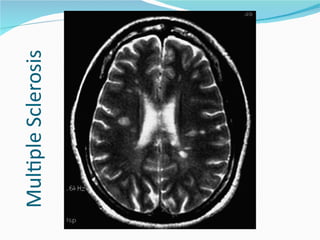

• #47 MRI of a 26-year-old woman with progressive disequilibrium and bidirectional horizontal nystagmus shows the periventricular areas of demyelination that are characteristic of multiple sclerosis.